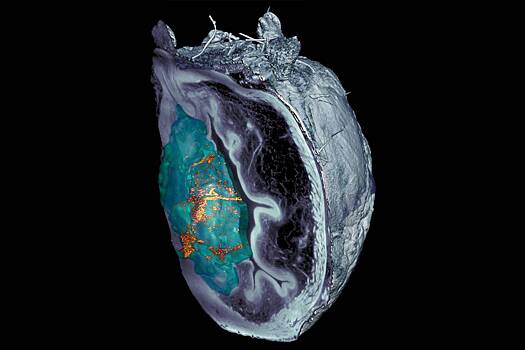

Наномашины представляют собой пористые сферы из кремнезема, на поверхности которых находятся различные молекулы, например, фермент уреаза. Уреаза — это белок, который расщепляет мочевину, а выделившаяся энергия используется для перемещения наночастиц. Другим важным компонентом является радиоактивный йод, который применятся для лечения опухолей.